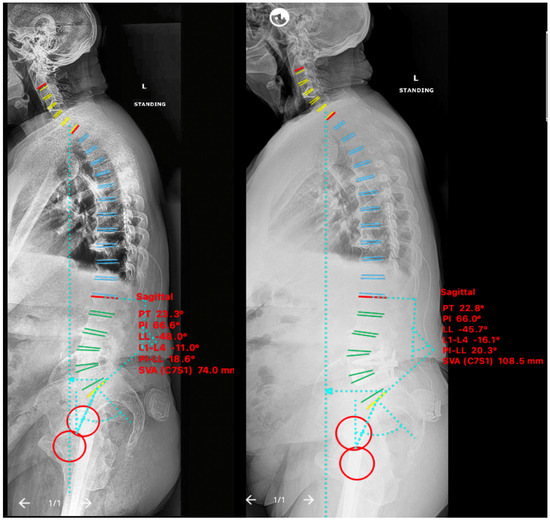

2.4.2. Case II

2.4.3. Case III